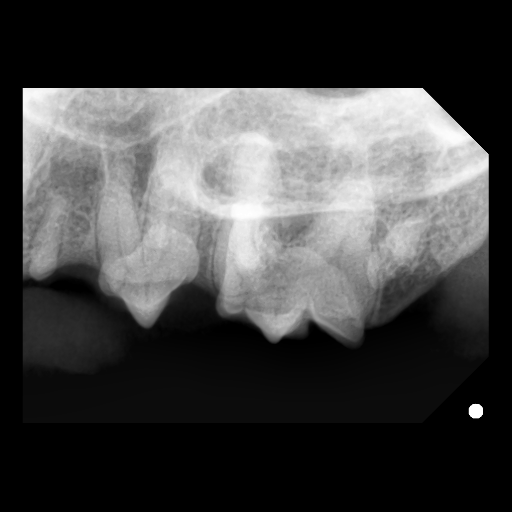

吸収病巣のレントゲン

こちらの写真は一部が吸収病巣になって溶けてしまっているレントゲン写真です。

肉眼では明らかに判断することは意外と難しいです。